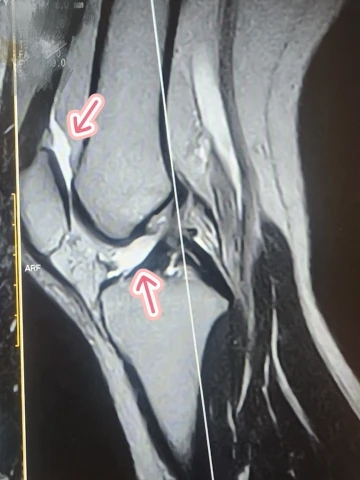

半月板も靭帯も損傷なく

『膝自体は元気』である事が分かりました??

ただ、膝を打撲した事による炎症と

それを守ろうとして

関節液(水)が少し溜まってるそうで

(抜かなきゃいけないほどではない)

ガチの私の膝(笑)↓(白いとこが水)